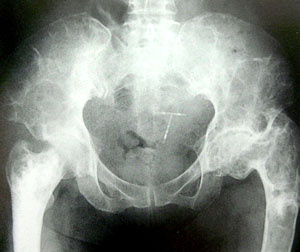

一、病灶多發生於四肢長骨,尤以股骨和脛骨為多見,其次為肋骨、顱面骨、骨盆和手、足小骨,而脊柱較為少見。

二、X線上,病灶的密度常有差異,取決於病理成分,病灶如主要為纖維組織常表現為囊狀透光區;如主要為砂礫樣鈣化新生骨者常呈磨砂玻璃狀;如新生骨鈣化較多時則表現為一片明顯的增白區。每一病灶,可以上述表現按不同比例組合出現。

3、位於長、短管狀骨和肋骨的病灶多發生於骨幹或骨骺端,病骨膨脹而變粗大,常呈單房透明或磨砂玻璃狀,範圍較大,其中可有緻密骨嵴沿骨長軸方向走行向內凸出,使病灶呈不完全的分房狀如“絲瓜囊”。有時在病灶內可見或大或小的片狀鈣化影。

骨纖維異常增殖症①變形性骨炎型:常為多骨型病變表現,其特點是顱骨增厚,顱骨外板和頂骨呈單側泡狀膨大,骨內板向板障和顱腔膨入,增厚的顱骨中常見局限和瀰漫的射線透明區和濃密區並存,這種骨吸收與硬化並存極似Paget變形性骨炎的表現。顱骨擴大和硬化,可從額骨擴大到枕骨。面部受累可導致眶和鼻腔狹窄及鼻竇腔消失,此型約占56%。②硬化型:此型多見上頜肥厚,可致牙齒排列不整,鼻腔、鼻竇受壓變小。上頜骨受累多於下頜骨,且多為單骨型。損害呈硬化或毛玻璃樣外觀。相反,下頜骨損害多見於多骨型,表現為孤立的骨壁光滑且可透過射線。此型約占23%。③囊型:顱骨呈孤立或多發的環形或玫瑰花形缺損,缺損從菲薄的硬化緣開始,其直徑可達數厘米。孤立的損害有似嗜酸性肉芽腫,多發的缺損可誤認為HandSchüllerChristian病,偶有數種X線類型出現於同一個體上。此型約占21%。套用CT或MRI檢查,能明確病變的位置和範圍,且能顯示與軟組織的聯繫。定期檢查可動態觀察病變的發展程度,對選擇術式進路、減少併發症和估計預後甚為重要。